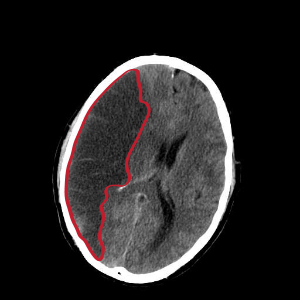

CT scan slice of the brain showing a right-hemispheric cerebral infarct (left side of image). | |

Computed tomography (CT) and MRI scanning will show damaged area in the brain, showing that the symptoms were not caused by a tumor, subdural hematoma or other brain disorder. The blockage will also appear on the angiogram.